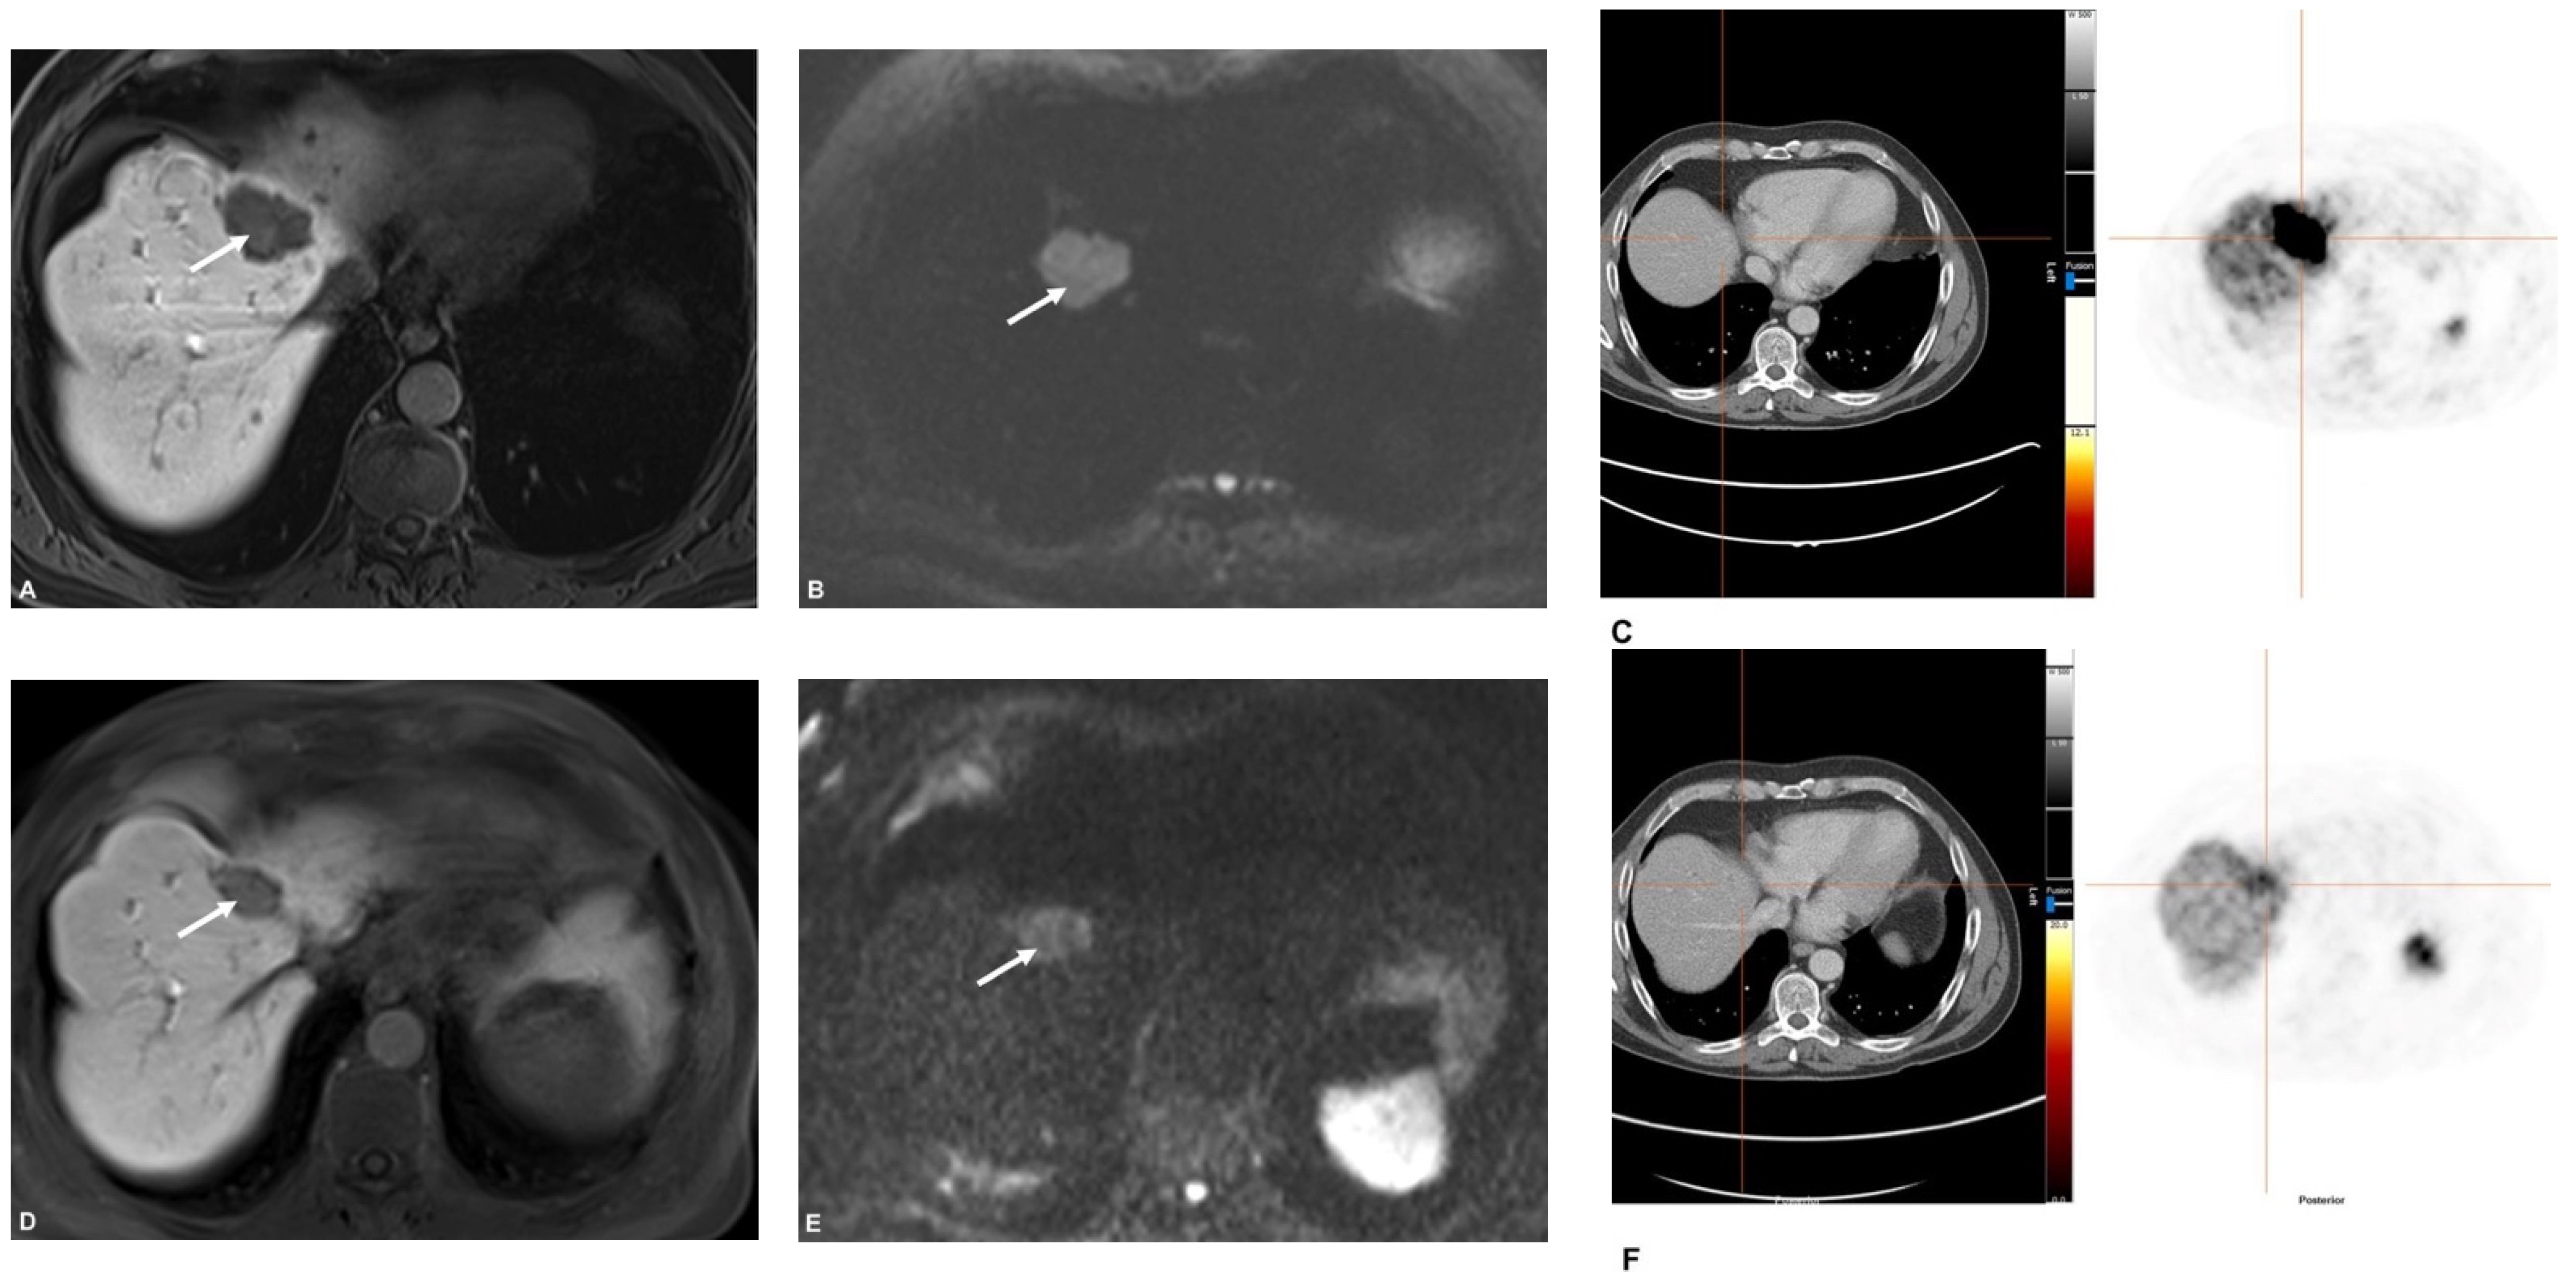

68Ga-DOTATATE PET/CT and MRI with Diffusion-Weighted Imaging (DWI) in Short- and Long-Term Assessment of Tumor Response of Neuroendocrine Liver Metastases (NELM) Following Transarterial Radioembolization (TARE)

2.3. MR Imaging

2.4. PET/CT

2.5. Image Analysis